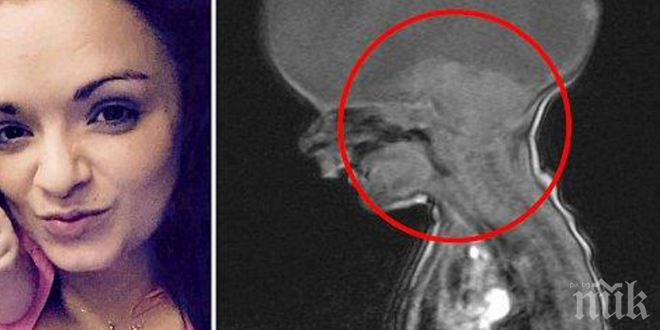

След като лекарите й съобщават, че трябва да роди, я приемат по спешност и се ражда нейният неочакван син. Дотук добре, има доста такива истории, но жената получава още един шок, когато лекарите съобщават, че нейното бебе страда от много рядко заболяване – holoprosencephaly. Това представлява малформация на мозъка – той не е напълно оформен, повечето деца умират още в утробата.

Жената споделя, че лекарите са й казали, че нейният син няма шанс да оцелее – давали са му най-много три часа, три дни. Жената си спомня, че всичко е станало много бързо, не е знаела, че е бременна, родила е дете, а накрая са й казали, че то може да умре - всичко това в рамките на няколко часа. Детето кръстили Аарон и противно на всички очаквания, той диша самостоятелно, отваря си очичките и напуска болницата след 8 седмици наблюдение.

Въреки че Аарон е доказал, че е жизненоспособен, лекарите не вярват, че някога ще надхвърли психичното състояние на новородено. Преди няколко седмици той изненадал всички – повтарял е думичката, която стопля сърцата дори на най-студенокръвните хора – „мама“. Жената добавя, че се е разплакала и това е било уникален момент за нея и за цялото семейство.